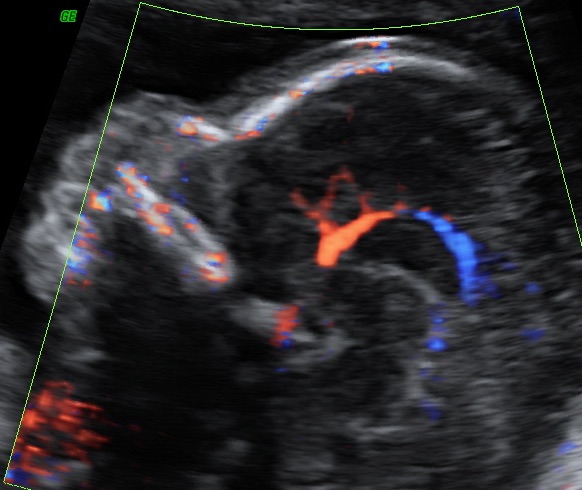

L’ecografia in Ostetricia

L’ecografia è entrata prepotentemente nel mondo dell’ostetrica e della gravidanza, tanto da rivoluzionarne tutto l’approccio e creare una nuova branca, ovvero quella della medicina fetale.

La medicina fetale attraverso l’uso degli ultrasuoni ha permesso lo studio del comparto uterino e fetale dando anche la possibilità di effettuare procedure diagnostiche e terapeutiche invasive.

In particolare, l’ecografia, nelle diverse settimane di gravidanza permette di monitorare il benessere fetale e di realizzare uno studio particolareggiato della struttura, valutarne l’accrescimento, con la possibilità attraverso complesse formule matematiche di determinare una stima del peso fetale.

L’ecografia del secondo trimestre, meglio conosciuta come ecografia morfologica, è il massimo concentrato delle potenzialità dello studio ecografico: questa è l’epoca gestazione in cui si ha il miglior rapporto tra le dimensioni del feto stesso e la risoluzione dell’apparecchio, al fine di eseguire un’analisi morfostrutturale. Si possono investigare estensivamente parametri della crescita e del benessere fetale, implementando lo studio con la visualizzazione e valutazione della vascolarizzazione fetale ed uterina. Una profonda conoscenza dell’anatomia fetale permette inoltre di realizzare un’ecografia genetica, valutando il rischio di patologie cromosomiche.

I moderni apparati consentono inoltre di arricchire la normale indagine ecografica bidimensionale con ricostruzioni tridimensionali e più recentemente anche quadridimensionali, ovvero con una modellazione solida in real-time.

L’ecografia ostetrica ha quindi un inestimabile valore diagnostico ma ha anche l’insostituibile ruolo di presentare ai futuri genitori il loro figlio, così da aumentarne la consapevolezza durante la gravidanza.

L’ecografia morfologica è infatti anche un momento in cui i genitori trovano rassicurazioni e risposte ai molti dubbi e domande.

Per una mamma, poter vedere il bambino che porta in grembo, essere rassicurata sulla propria salute e su quella del proprio figlio, ha un effetto positivo generale che influisce sulla percezione ed il buon andamento della gravidanza stessa.